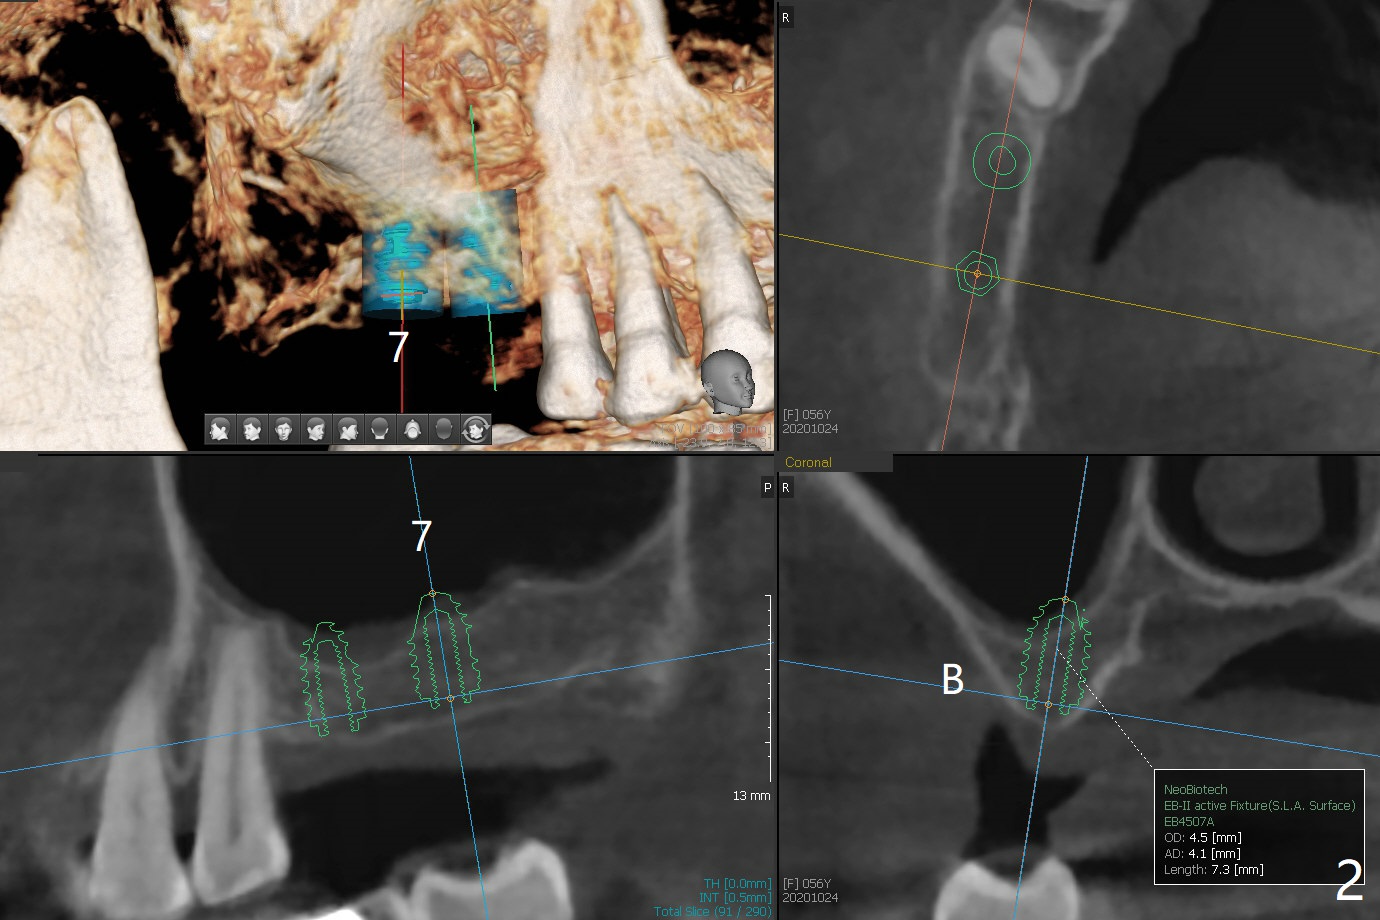

56岁女牙周炎,失去右上6,7以及右下1,后者缺牙间隙特别宽,其余切牙往颊侧移位(flare,病人不愿意拔除,图一)。右上植牙修复后(图二,三),下前牙种植(图四,五(选择窄植体)),建立正常覆盖,同时在邻近切牙唇侧植骨(图七,八:红线)。四-六个月后做局部矫正:使用植牙作为支抗将颊侧移位的前牙(牙冠)往舌侧推移(图七,八:蓝箭头),而牙根可能往唇侧移位(图六:红箭头),所以事先植骨(图七,八:红线)重要。矫正后3-3舌侧放置钢丝树脂固定。Jennifer: #25 implant and crown should be lingualized, as compared to the rest of the lower incisors (flared). After osteointegration, ortho will be conducted to correct the flaring using #25 implant as an anchor.